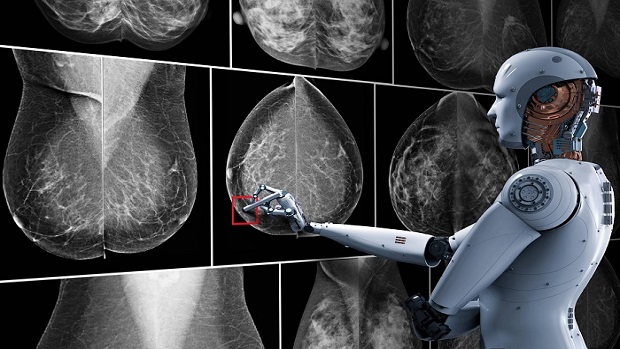

Mamografi hakkında 10 soru 10 cevap

Meme ultrasonografisi tarama veya tanı amaçlı mamografi tetkiki yapılmış, yoğun meme dokusuna sahip hastalarda tamamlayıcı tetkik olarak 40 yaş altı hastalarda birincil işlem olarak koltuk altı bölgelerinin (aksiler bölge) değerlendirilmesinde ve biyopsi işlemlerinde kılavuz yöntem olarak yapılmaktadır.

40 yaşından itibaren tarama amaçlı rutin olarak her yıl mamografi tetkiki yapılmalıdır. Yoğun içerikli meme dokularında, mamografik hassasiyet azalan olgularda ve mamografide bulgu saptanan olgularda, mamografiyi tamamlayıcı olarak ultrasonografi yapılmalıdır. 50 yaş üzeri kadınlarda da herhangi bir yaşta olabileceği gibi, ultrasonografi rahatlıkla yapılabilir.

Yüksek riskli gruba dahil kadınlarda rutin yıllık mamografi ve ultrasonografi ile birlikte yıllık aralıklarla meme MR incelemesinin de rutin takiplere eklenmesi önerilmektedir. Bunun için hasta riskinin doğru hesaplanması önemlidir.